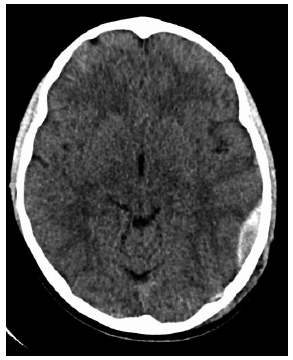

Menino sofreu queda há aproximadamente 4 horas. Estava andando de skate na rua e caiu de costas, no chão, e bateu a cabeça. Apresentou vômitos, está um pouco sonolento; fez a seguinte tomografia, sem contraste.

O diagnóstico é de hematoma